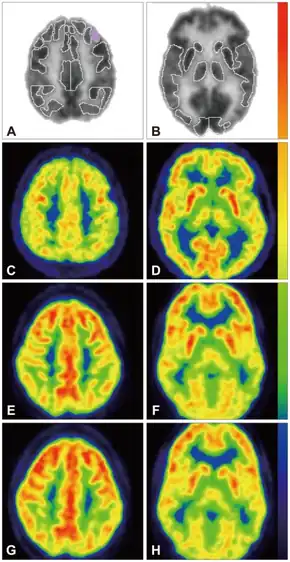

- ↑ Fernell E, Watanabe Y, Adolfsson I, Tani Y, Bergström M, Hartvig P, et al. (May 1997). "Possible effects of tetrahydrobiopterin treatment in six children with autism--clinical and positron emission tomography data: a pilot study". Developmental Medicine and Child Neurology. 39 (5): 313–8. doi:10.1111/j.1469-8749.1997.tb07437.x. PMID 9236697. S2CID 12761124.